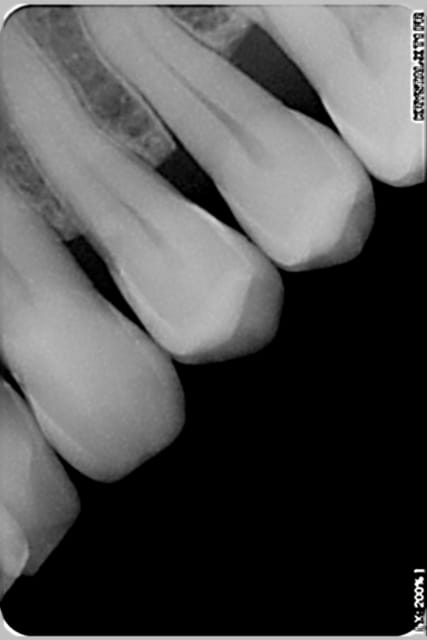

quelques retro faites en 2009 (critiquables, je sais, ça va mieux aujourd'hui)

Radio 36 2009 liviaq - Eugenol

Radio 16 2009 alhcqr - Eugenol

Radio 25 2009 pd2mbc - Eugenol

Radio 46 2009 eomewu - Eugenol

Voir images

On peut y voir une remodelage osseux, de tartre, l'usure de la canine